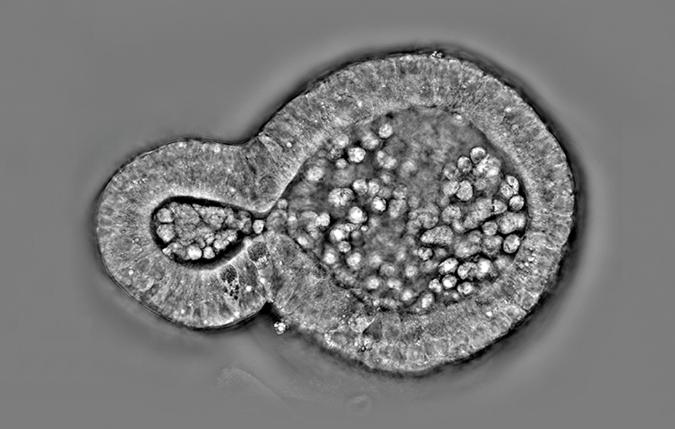

Con la nuova modalità di imaging brightfield a colori e le funzionalità di scansione a anteprima ampia, i ricercatori possono ottenere approfondimenti più dettagliati negli studi su sezioni di tessuti. La piattaforma consente l'integrazione fluida di dati strutturali complessi, ottenuti tramite sezionamento ottico 3D, con informazioni istologiche da colorazione H&E o immunoistochimica. Questa integrazione arricchisce la nostra comprensione della morfologia e della dinamica dei tessuti, accelera i progressi in anatomia patologica clinica e diagnostica e contribuisce a preparare la strada per il futuro della medicina personalizzata.

HT-X1™ Plus è ottimizzato per lo screening ad alto rendimento, rendendolo particolarmente adatto per la ricerca nello screening di farmaci basato su immagini ad alto contenuto. Dotato di una fotocamera ad alte prestazioni CXP e algoritmi di ricostruzione delle immagini alimentati da Intelligenza Artificiale, la piattaforma eccelle sia nella copertura che nella velocità di acquisizione. Il suo ampio campo visivo di 308 μm x 308 μm e la rapida capacità di scansione 3D, permettono ai ricercatori di analizzare in modo efficiente un'intera piastra a 96 pozzetti in meno di 30 minuti. Questa efficienza consente esperimenti su larga scala con una precisione e coerenza senza pari, portando a un'acquisizione dei dati più rapida e affidabile, che accelera significativamente il processo di scoperta dei farmaci.